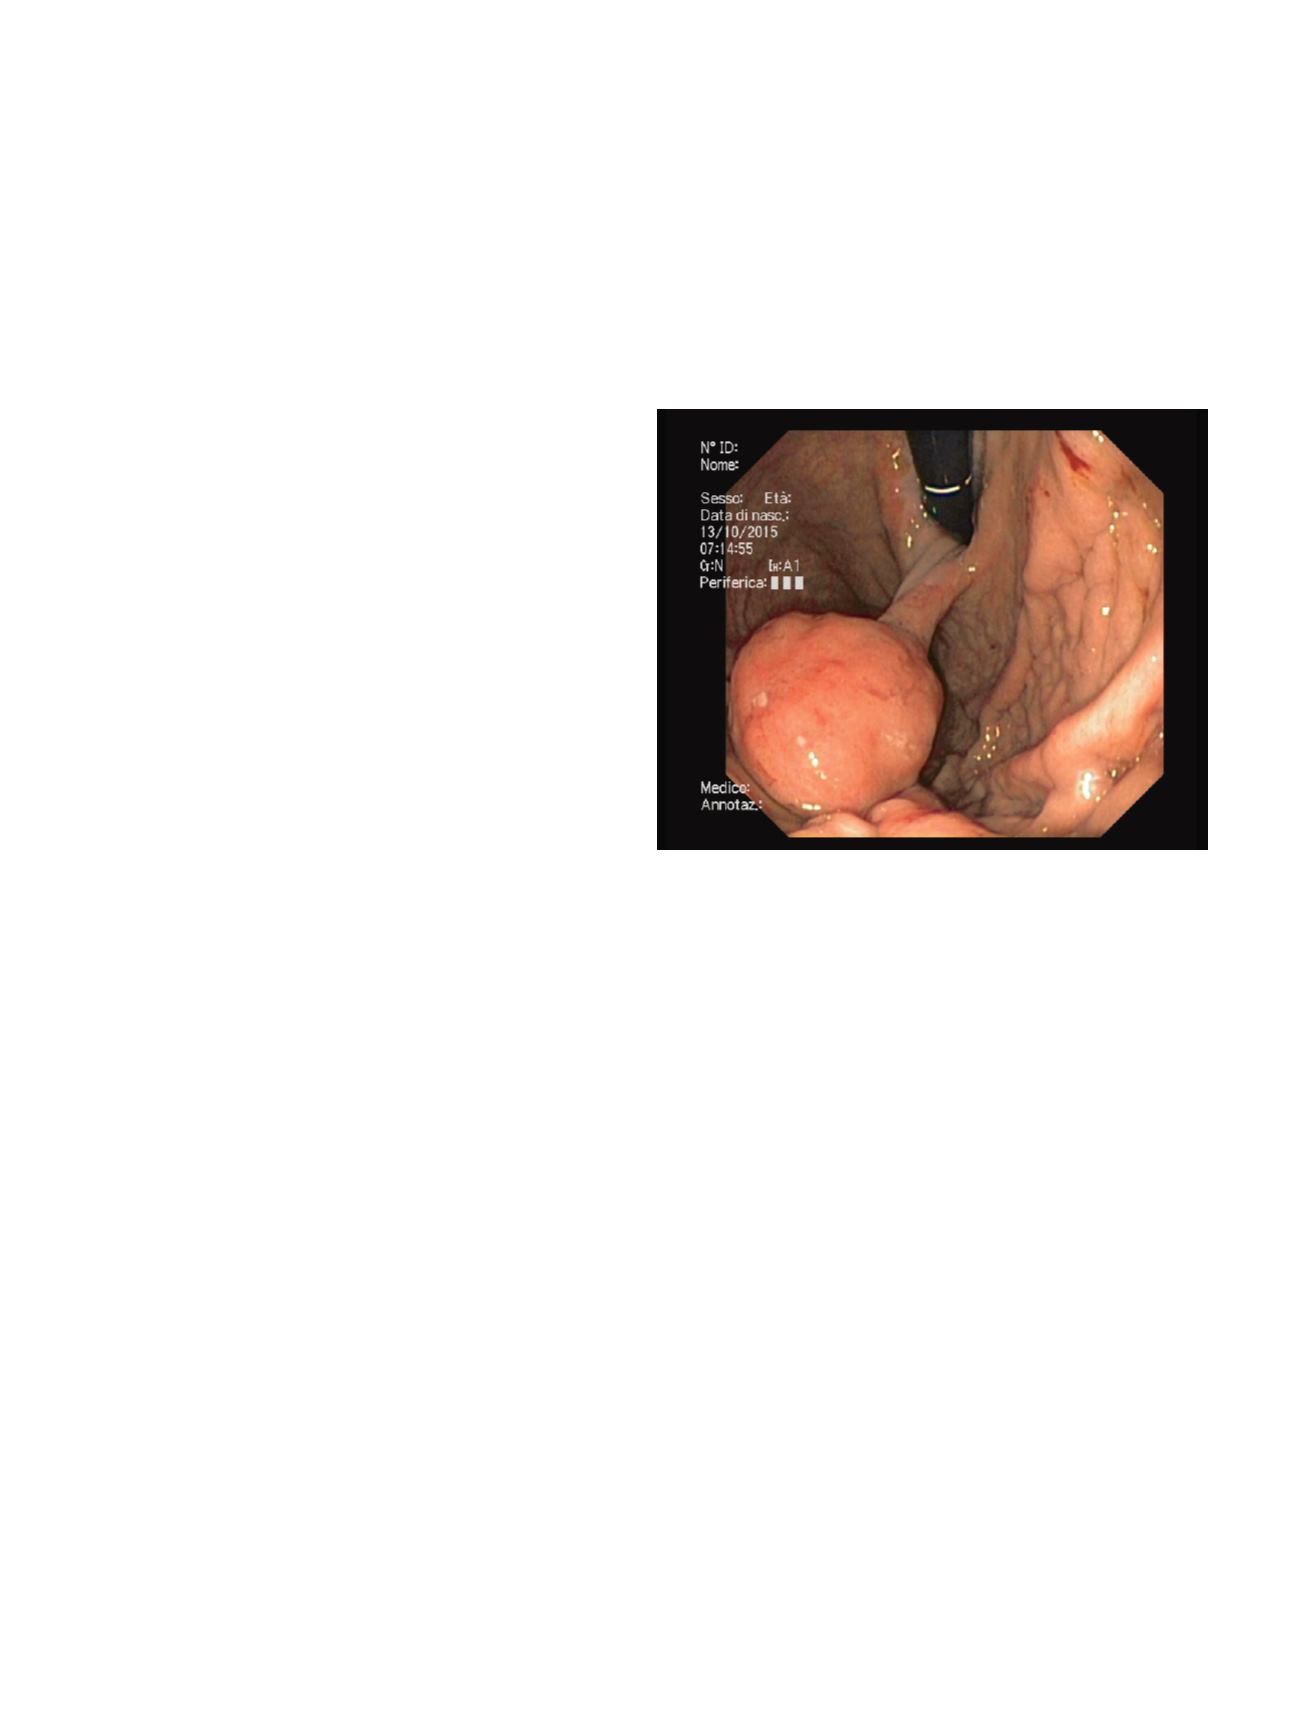

ENDOSCOPIC RESECTION OF A LARGE PYLORIC GLAND ADENOMA

OF THE CARDIA

Togliani T.*, Mantovani N., Vitetta E., Savioli A., Troiano L., Pilati S.

S.S.D. di Endoscopia Digestiva, Azienda Ospedaliera Carlo Poma,

Mantova, Italy

Material and methods:

A 69-year-old man presented with iron-

deficiency anemia. Colonoscopy was unrevealing. Upper GI

endoscopy showed a 4 cm round peduncolated lesion hanging in

the gastric fundus from the cardia, with some small erosions on

the overlaying mucosa. At EUS the head of the polyp consisted of

a slightly hyperechoic inhomogeneous submucosal mass with

internal anechoic cystic spaces; the superficial mucosal layer was

normal; no Doppler-positive structures were visible in the stalk;

no regional lymph nodes were visible. Afterwards, using a large

working channel gastroscope, we put an endo-loop at the base of

the stalk, we resected the lesion with a snare and we retrieved the

polyp for histology.

Results:

No early complications occurred and the patient was

discharged two hours after the procedure. Histology revealed a 4.5

cm pyloric gland adenoma with no dysplastic alterations; the

superficial epithelium showed a lymphocytic Helicobacter pylori-

positive chronic gastritis. At the time of writing this paper neither

an upper GI endoscopy nor a blood cell count have been repeated

yet.